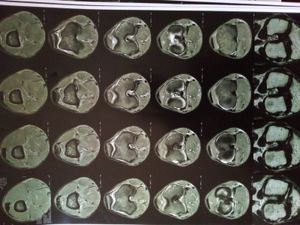

Estou afastado do trabalho por uma lesão de joelho, e o exame mostra um cisto que indica ruptura parcial de menisco, que só pode ser reparada com um tratamento. O custo pode variar entre 7 e 10 mil reais. O tratamento garante que eu volte a jogar futebol, correr e praticar outros esportes. A lesão do colateral se regenera, a do menisco não regenera sozinho. Embora eu faça as sessões de fisioterapia, elas garantem que eu volte a caminhar normalmente mas sem garantia de poder jogar. A colaboração de qualquer valor, mesmo que mínima já ajuda muito! Desde já agradeço de coração.